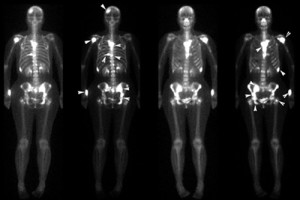

Основу процедуры составляет радиоизотопное аппаратное сканирование тела или отдельных его частей, в результате которого получается снимок двухмерного изображения, где видны проблемные очаги. Процедура занимает несколько часов. Для получения более ясной картины, а также для того, чтобы гамма-лучи возымели воздействие, в организм пациента вводится специальный радиоактивный индикатор (контрастное вещество). Заметим, что сцинтиграфия костей гораздо эффективнее, нежели обычная рентгенография.

Через 1-2 дня после проведения процедуры результаты будут готовы. Заметим, что сканирование производит врач-технолог, а изображение расшифровывает радиолог (эксперт по ядерной медицине). Сцинтиграфия скелета дает представление о том, есть ли новые зоны роста или расщепления костей.

К нормальным показателям относится: равномерное распределение контрастного вещества, на снимке не выявлено областей большого или незначительного скопления изотопов.

Признаки патологии: на снимке четко видны участки большого скопления радиоактивного индикатора (яркие пятна). Эта картина может свидетельствовать о том, что:

Незначительное количество индикатора – признак множественной миеломы (разновидность рака) или недостаточное кровоснабжение участка. На снимке эти области будут затемнены.

Остеосцинтиграфия — это метод визуализации, который используется для оценки состояния костей с помощью радиоактивных изотопов. Процедура включает введение радиофармацевтического препарата в вену, после чего пациент проходит сканирование с помощью специального устройства, которое фиксирует излучение, исходящее от препарата, и создает изображения костей.